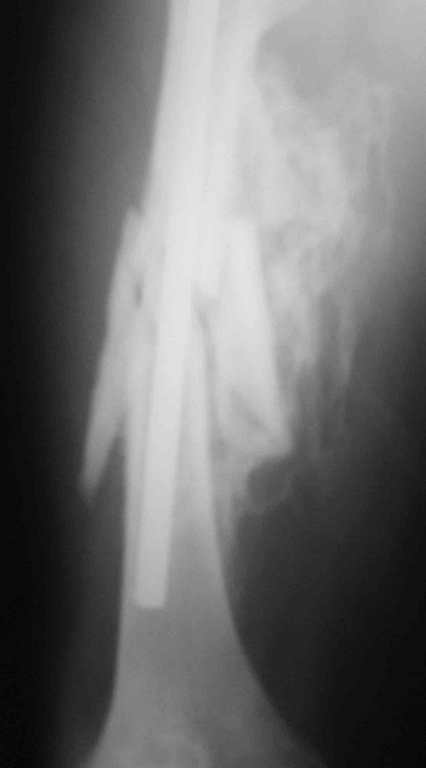

Re: 32- летний пациент с переломами обоих бедер после неудачного оперативного и консервативного лечения.

Иллюстрации к сообщению

а) Наложить односторонный одноплоскостной аппарат внешней фиксации на бедро, синтезированное стерднем ЦИТО. Сам стержень "забить" глубже. Стнржни провести непросто, но вполне реально. По стержню делается дистракция в аппарате (Методика из немецкого журнала ортопедия, 1996 год).

Вышеизложенная ситуация Вами не столь трагична, если бы в Вашем арсенале использовался метод чрескостного остеосинтеза в комбинации с интрамедуллярным остеосинтезом с блокированием. В данной ситуации (справа)удаление стержня ЦИТО можно совместиь с остеотомией/кортикотомией на вершине деформации с наложением дистракционного аппарата с последующим исправлением деформации и длины сегмента, а вторым этапом ЗИО. В отношении другого бедра ситуация анологичная, только без удаления металла. Если подобные методики у Вас не используются, сочувствую!

Уважаемый Антон.Исходя из Вашего материального положения!! и наличия хорошего, грубого омозоления, равности длины конечностей и судя по снимкам не очень выраженной антекурвации, но выраженной контрактуры коленных суставов: чтоб не упустить время разработки суставов и активизировать больного, необходимо справа удалить стержень, рассверлить канал и произвести ЗИМО более толстым неблокир. стержнем т.к. на этом уровне можно получить устойчивый остеосинтез, после чего активизировать и дозированная, упорная ЛФК, а дальше после восстановления функции ,время покажеть.

О происхождении такого запущенного случая- мой коллега работает экспертом ВТЭК и тянет в отделении и не такие казусы. Сегодня была сделана операция удален стержень из бедра и установлен стержневой аппарат из 2 опор, слева подвижности не наблюдалось, продолжается ЛФК. При необходимости позднее будет выполнена надмыщелковая корригирующая остеотомия. Спасибо всем за советы.